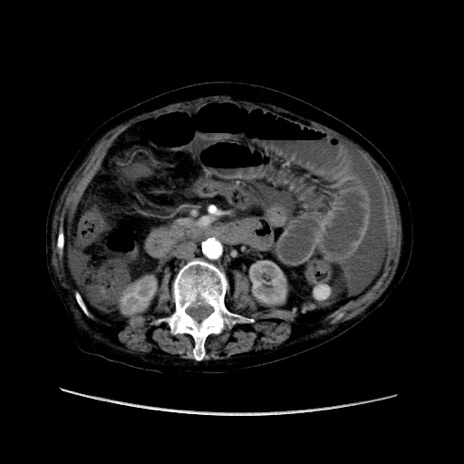

症例31(横断像)

【症例】80歳代 女性

【主訴】腹部膨満感

【現病歴】他院にて肝硬変にてフォロー中。1週間前から便秘、腹部膨満感、臍部腫瘤あり受診となる。

【既往歴】肝硬変

【身体所見】腹部膨隆あり、皮膚変化なし、疼痛なし。

【データ】WBC 4600、CRP 0.25